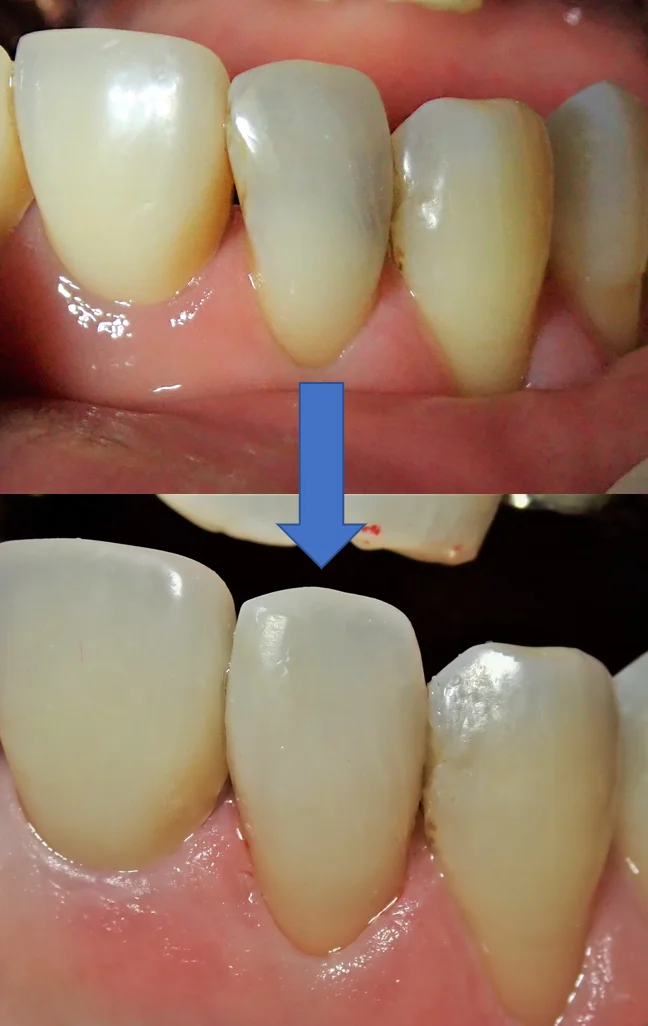

さて、本日は前歯部のダイレクトボンディングの症例写真です。

まずは術前の状態です。

歯の表側から見た状態です。

どこが虫歯か分かりますかね?

今回は結構色が透けているので、なんとなく虫歯になってるっぽいなと一般の方でも分かるかと思いますが・・・

表側がこんな感じで

最後に術前術後の写真を載せて終了したいと思います。